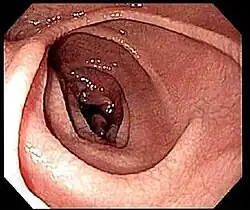

Imagem do duodeno de uma pessoa com doença celíaca obtida por endoscopia, na qual se pode observar pregas serrilhadas e a aparência semelhante a lama seca da mucosa.

Geralmente é realizada uma biópsia do duodeno ou do jejuno. São recolhidas entre quatro e oito amostras de tecido, já que as áreas podem não ser afetadas por igual e se a amostra for recolhida a partir de uma área saudável pode dar origem a falsos negativos.[39]

Na maior parte das pessoas com doença celíaca, o intestino delgado apresenta-se normal durante uma endoscopia. No entanto, existem cinco observações endoscópicas que sugerem doença celíaca: pregas mucosas serrilhadas, padrão em mosaico da mucosa (semelhante ao padrão de lama seca), proeminência dos vasos sanguíneos da submucosa e padrão nodular da mucosa.[67]